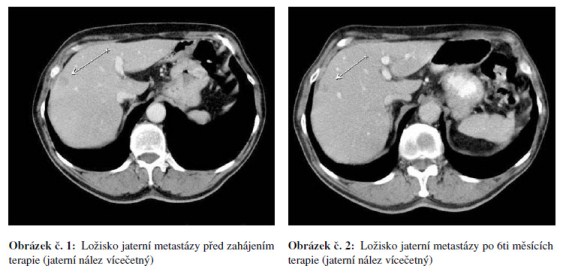

Po korekci hypertenze v říjnu 2008 zahájena chemoterapie FOLFOX 4 + bevacizumab. Kontrolní restaging po 6.s. chemoterapie v lednu a únoru 2009 ukázal parciální regresi jaterního postižení s normalizací hodnot CEA. Postižení nadále nevhodné pro chirurgické řešení a RFA. Pacient nadále bez proteinurie, hypertenze na monoterapii ACEI a stále přiměřená hematologická tolerance. Největší obtíží pacienta bylo ošetřování stomie při diarhoe dobře reagující na terapii loperamidem (Imodium®) nebo diphenoxylatem s atropinem (Reasec®). Jednou podán pouze bevacizumab pro nežádoucí účinky chemoterapie – průjmy. Vzhledem k výbornému stavu pacienta rozhodnuto pokračovat v další chemoterapii. Po dalších 3 měsících v květnu 2009 proveden restaging se stabilizací CT nálezu jaterních metastáz a trvající regresí CEA. Pacient nadále bez výraznějších toxicit, hypertenze nadále na monoterapii ACEI, bez proteinurie, hematologická tolerance přiměřená a diarhoe reagující na Reasec (diarhoe hodnotíme jako nežádoucí účinek flurouracilu). Vzhledem k dobrému stavu pacienta PS 1 opět rozhodnuto pokračovat v další chemoterapii. Po dalších 3 měsících restaging s trvající parciální regresí a nadále pokračováno v chemoterapii. V září 2009 pro vyčerpání pacienta při PS 2 pokračováno dále v monoterapii bevacizumabem. V říjnu 2009 na kontrolním CT hrudníku, břicha a pánve progrese onemocnění, dále progrese CEA a terapie bevacizumabem ukončena. Celkem podáno 20 serií Avastinu v režimu à 14 dnů (v kombinaci s FOLFOX 4 nebo samostatně).